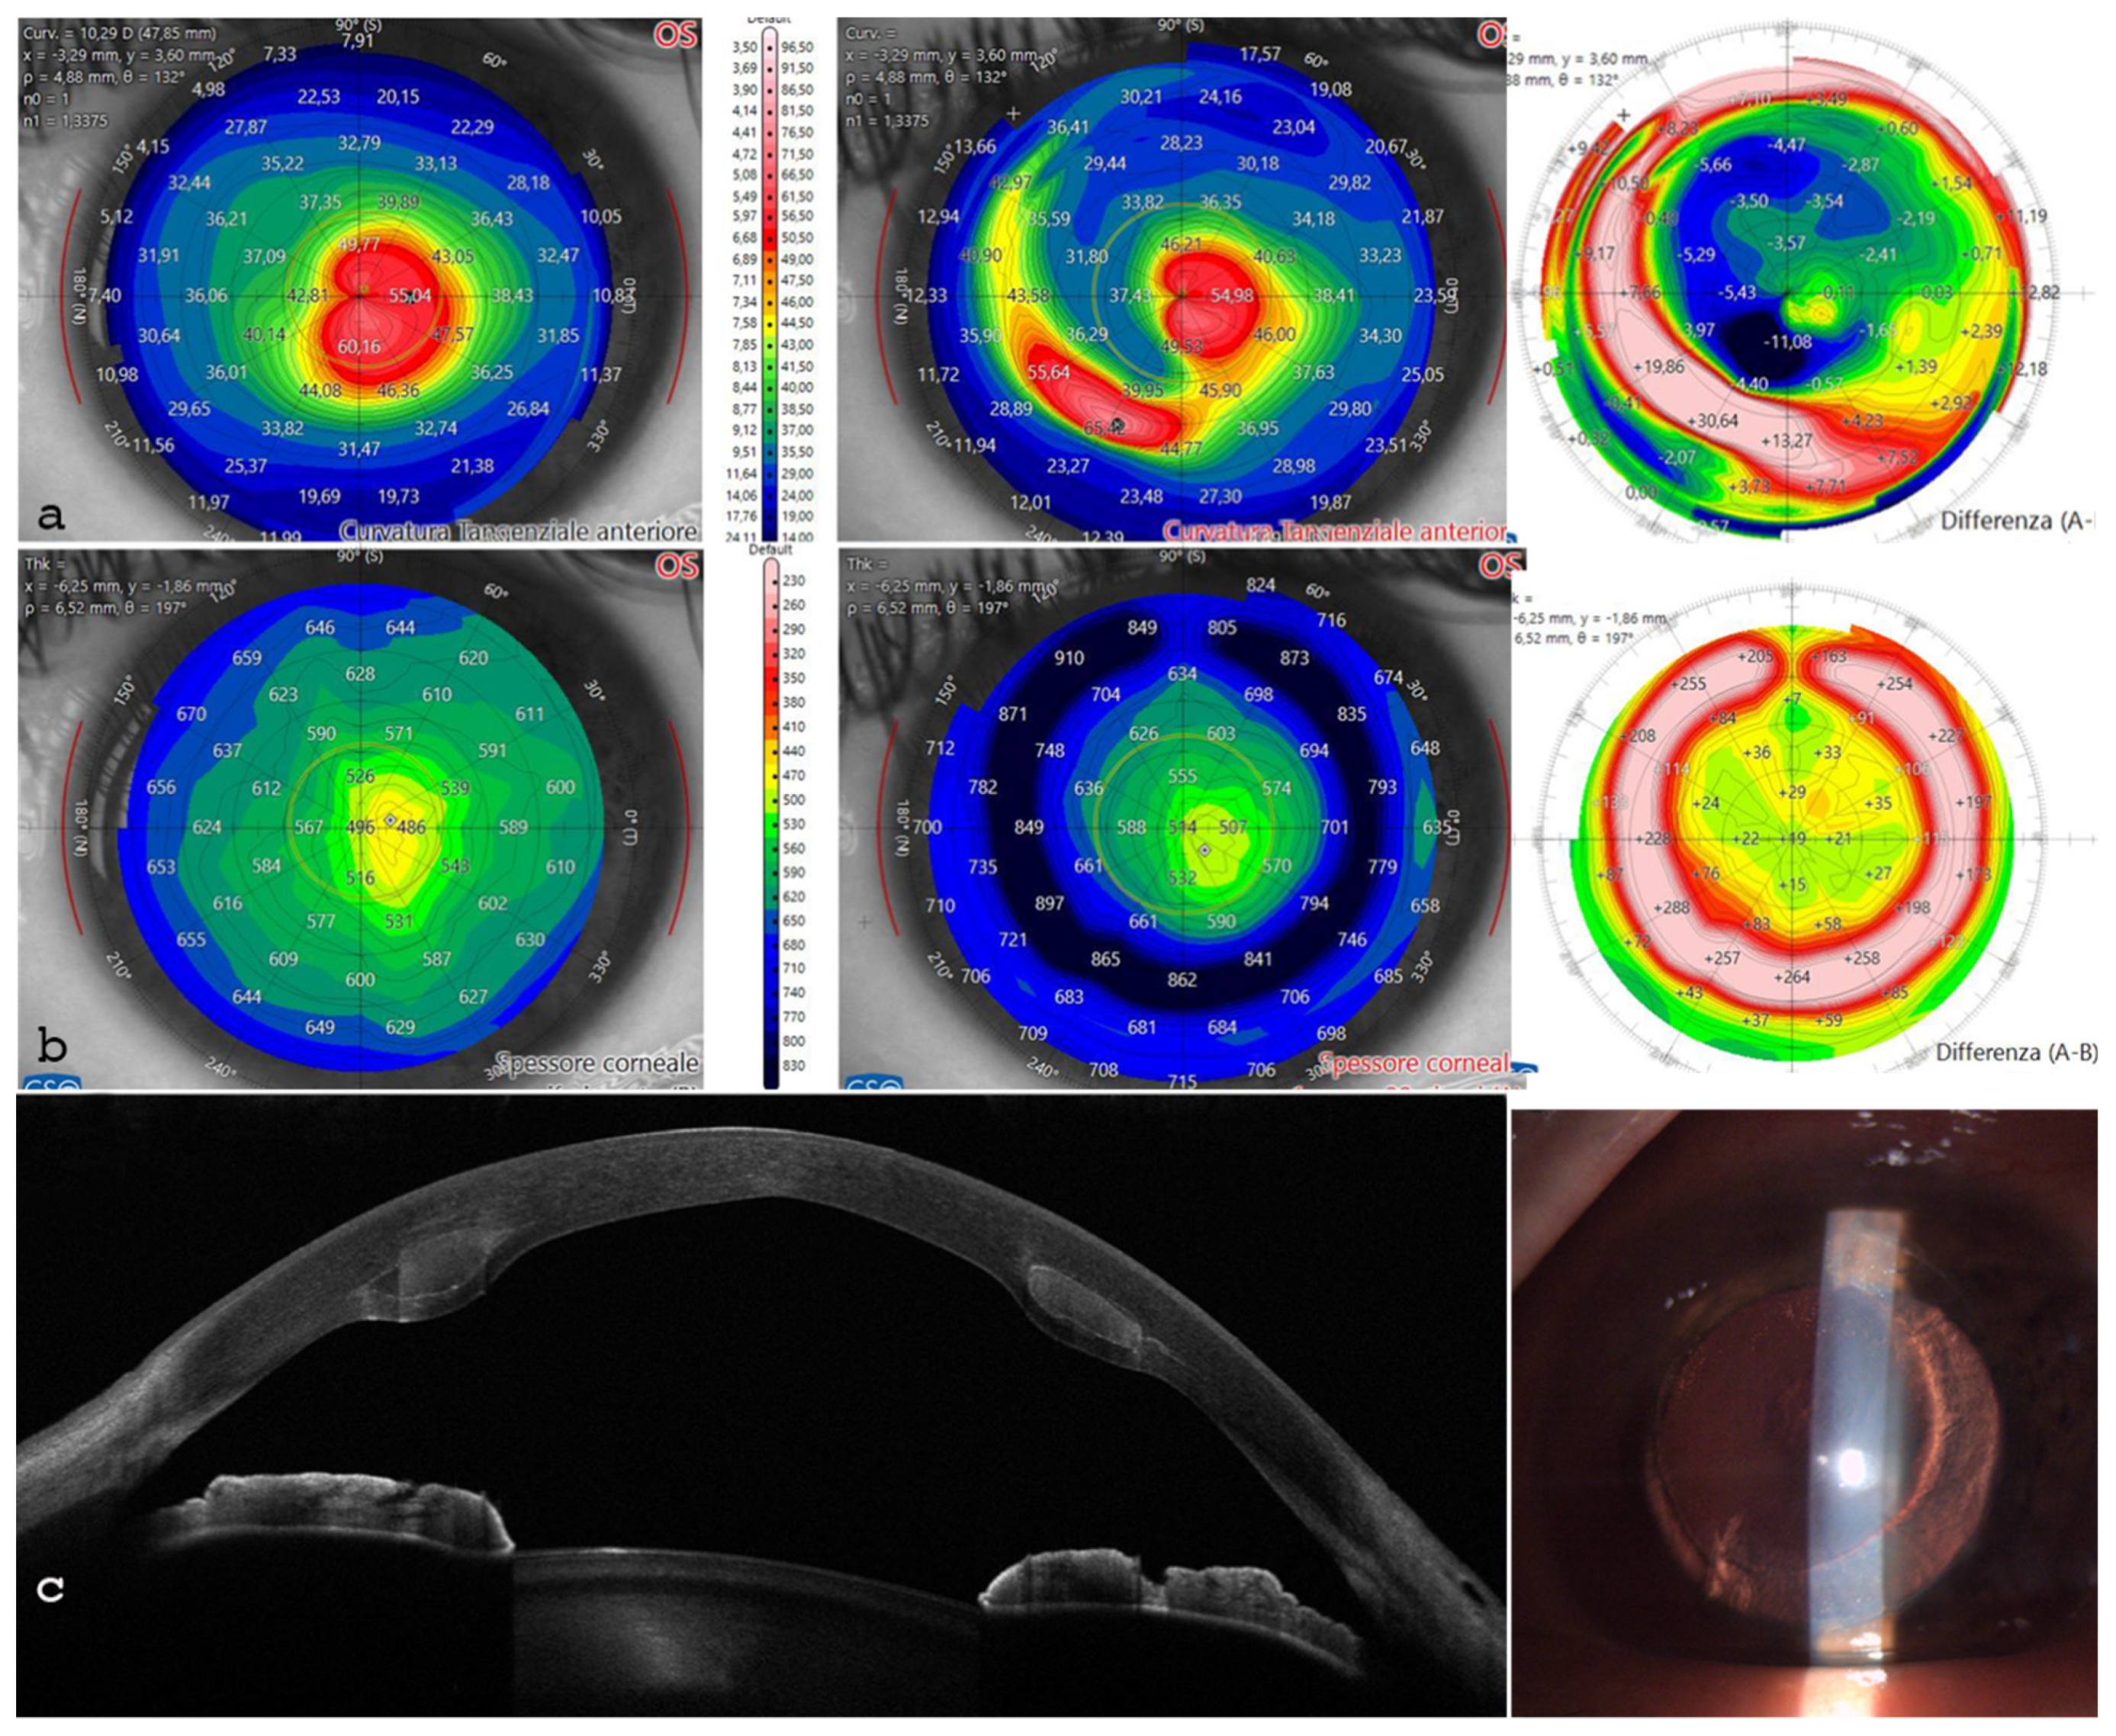

| Parameter | Preoperative | Postoperative |

|---|---|---|

| MPP 3 mm | 45.32 D | 44.30 D |

| SimK (K steep) | 53.53 D | 49.89 D |

| Astigmatism | −7.25 D@25° | −3.71 D@30° |

| Coma Aberrations | 1.49 D eq. @90 | 0.19 D @165° |

| Thinnest Point (µm) | 362 | 378 |

| MMP 3 mm | 54.64 D | 50.73 D |

| SimK (K steep) | 58.30 D | 45.75 D |

| Astigmatism | −7.25 D axis 25° | −4.75 D axis 30° |

| K Max | 62.41 D | 54.01 D |

| Coma Aberrations | 1.49 D eq. Axis 90 | D axis 165° |

| Thinnest Point (µm) | 443 | 486 |